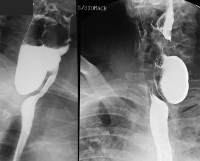

• Контрастная рентгенография пищевода. Является основным методом диагностики болезни, проводится в положении стоя в прямой и боковой проекциях с использованием бариевой взвеси. Позволяет определить локализацию, размеры, форму дивертикула, моторные нарушения органа и состояние окружающих его анатомических структур.